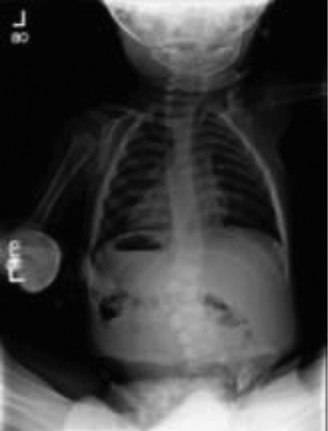

In room 2 you met a 3-year-old boy who is here with both of his parents. They report that over the last year, they have noticed that his spine “looks crooked” and they think that it is getting worse. On examination, you agree that his spine appears

to have a curvature, and you order x-rays (Fig. 10–19).

Figure 10–19

The x-ray is as above and you explain to the parents that their child has:

The correct answer is (C). This child has a hemivertebrae in the lumbar spine. The other options are not correct because A, B, and D assume that there is not an underlying structural issue with the osseus structures of the spine other than the curve itself. Given the obvious structural abnormality in the lumbar spine, this is not just a curve related to position at time of x-ray, so “E” is incorrect.